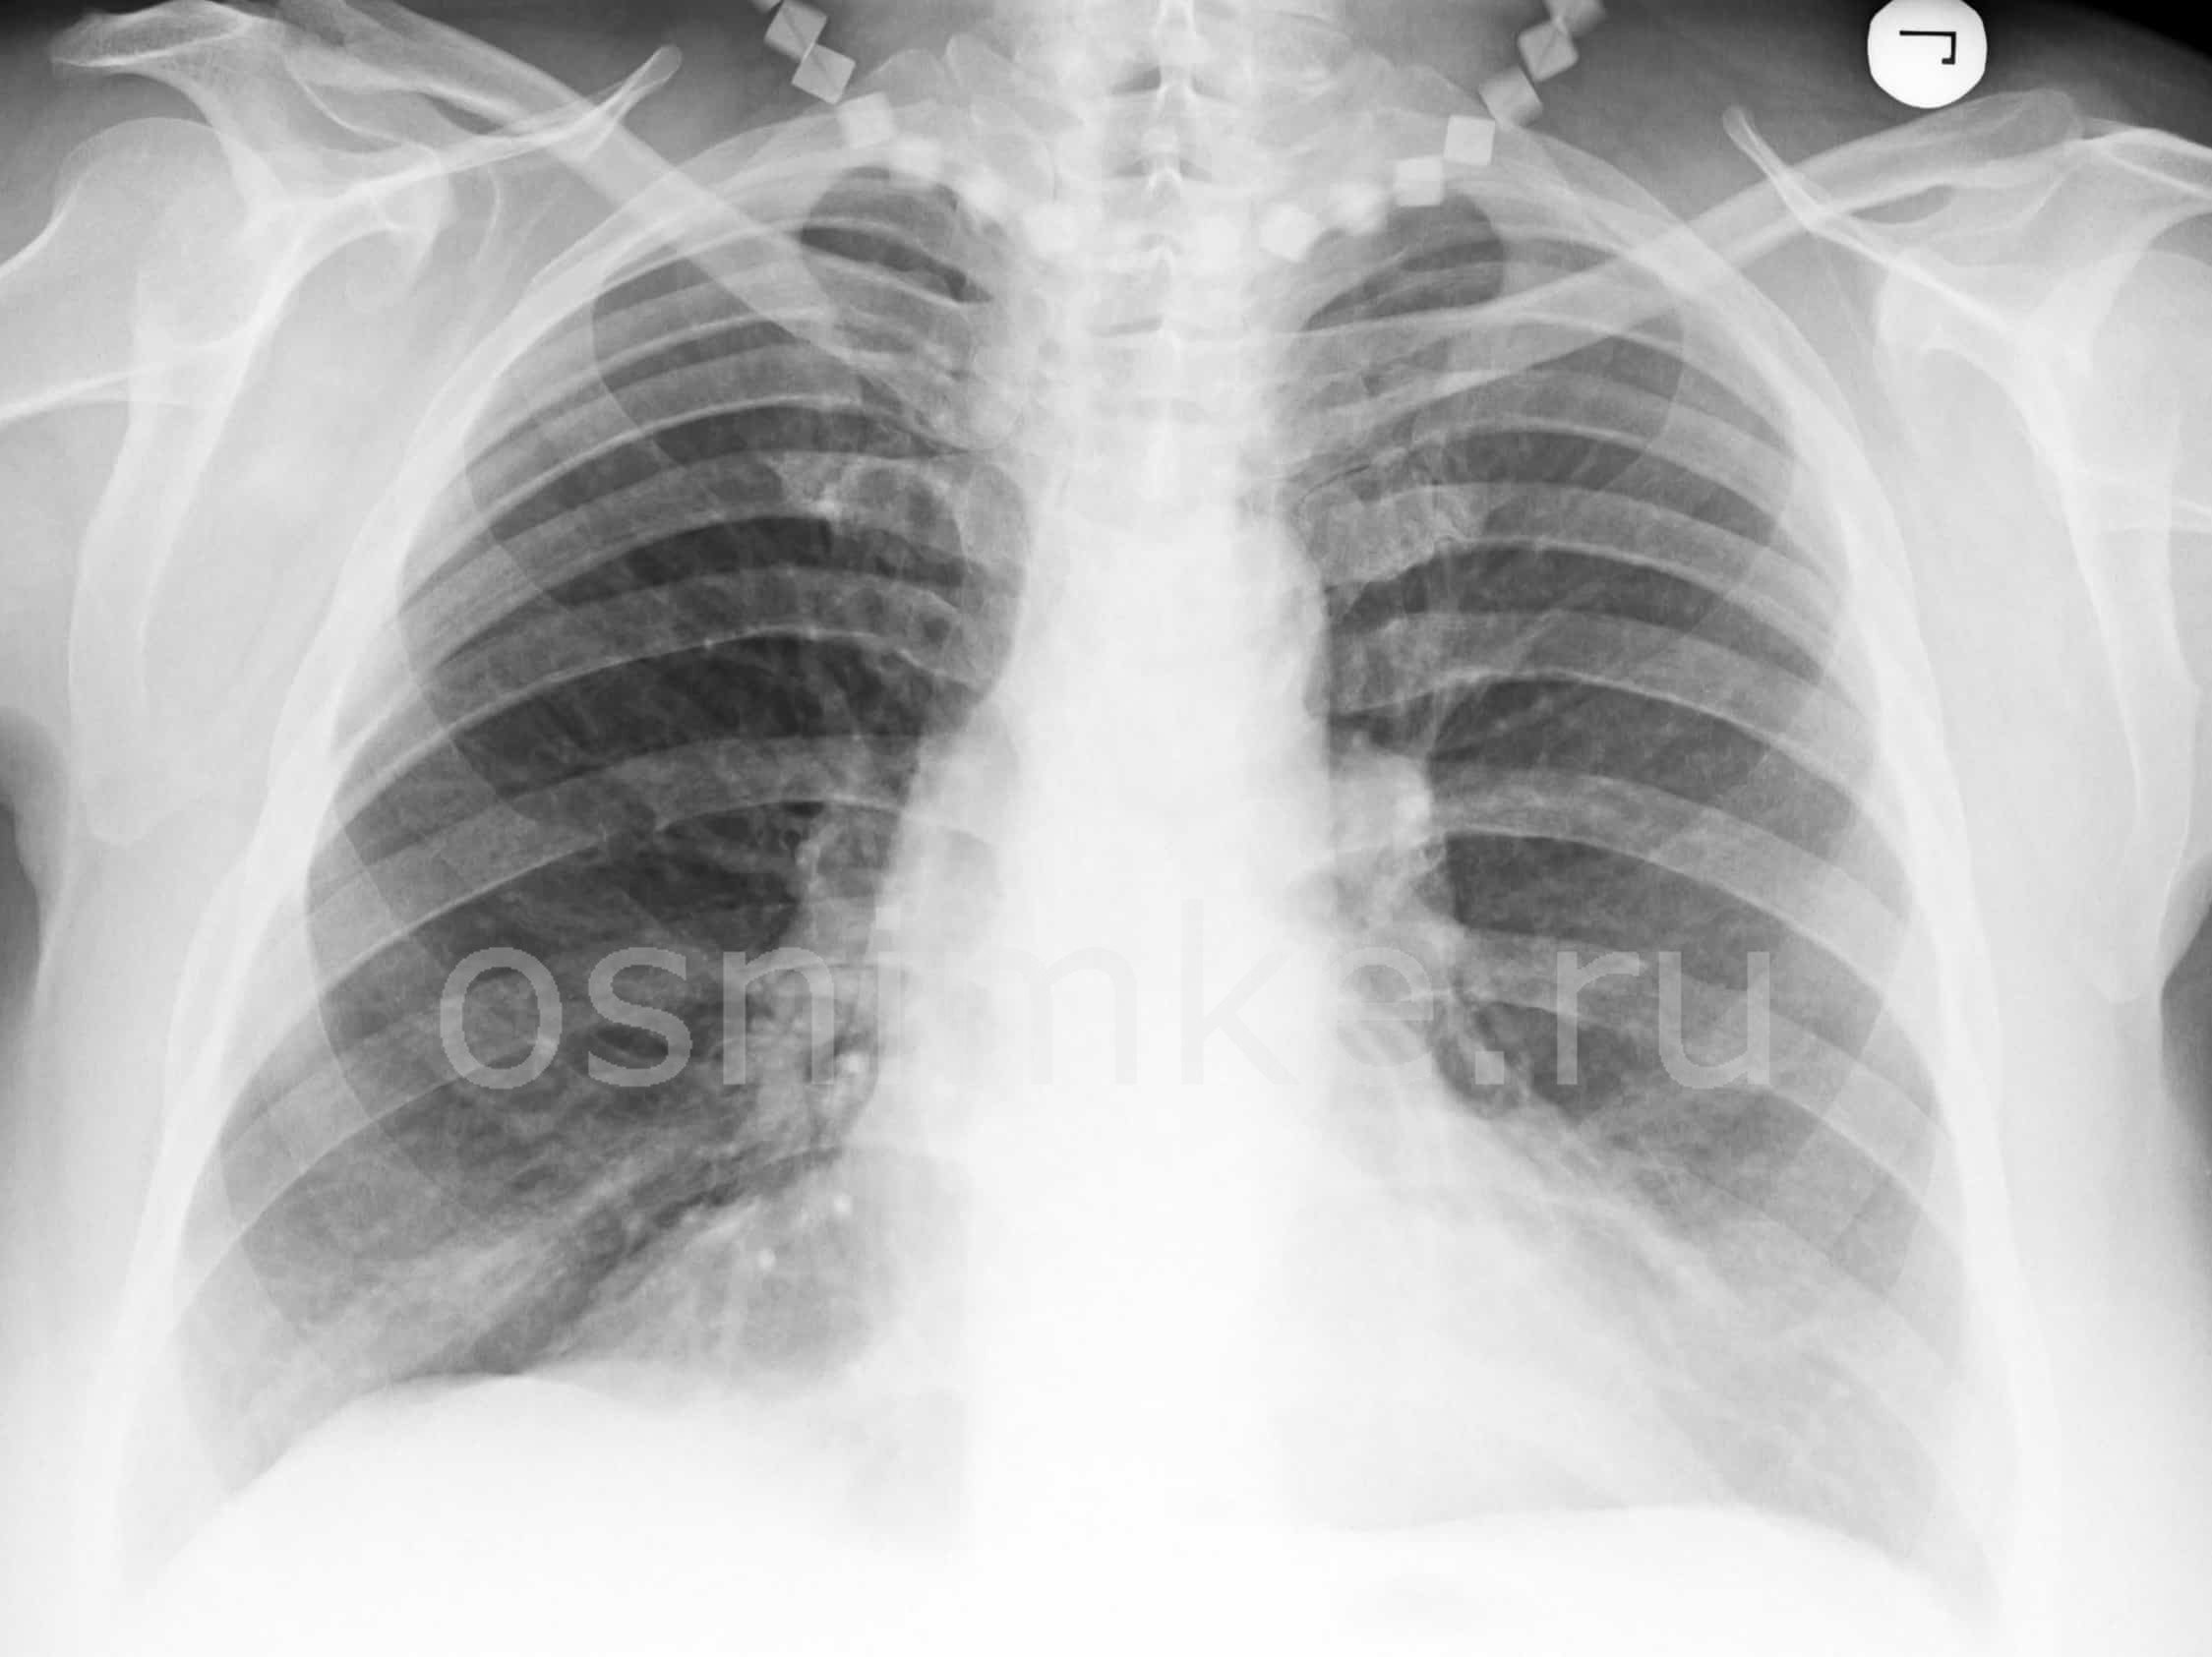

Рентгеновское и флюорографическое исследование имеют один и тот же принцип, но при диагностике пневмонии предпочтение отдается рентгену.

Флюорография позволяет выявить изменения в тканях легких на ранних стадиях, но не дает достаточно четкой рентгенологической картины для постановки точного диагноза.

Вместе с тем, коэффициент облучения при проведении процедуры гораздо меньше, чем при рентгеновском исследовании, поэтому флюорографию делают в профилактических целях, а рентген – непосредственно для диагностики патологических процессов при наличии соответствующих симптомов.